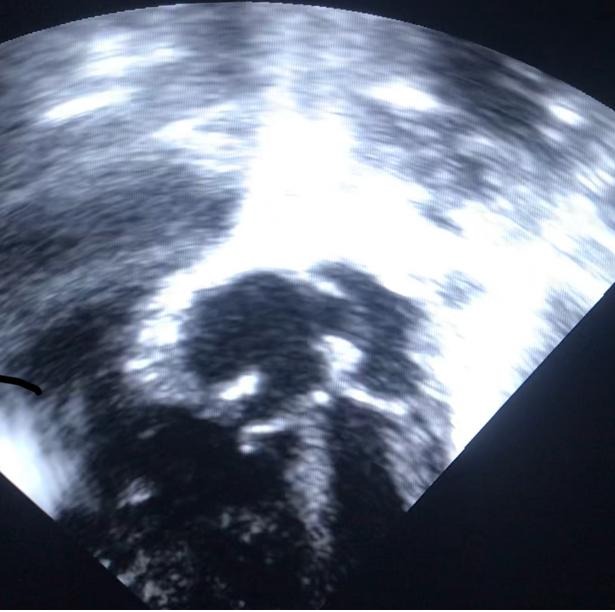

Hi, my name is Dr Cyprian Umeoguaju ( MBBS, MRCPCH), I am soliciting fund for Abubakar Abubakar. I started managing him since he was born. Following his birth, he had a complex congenital heart disease ( tricuspid valve dysplasia) which made him blue since birth. I managed him conservatively and he now needs cardiac surgery as his heart is beginning to fail and his parents cannot afford the huge cost required to help me get cardiac surgical care. I have referred him to FCC Lagos and the cardiac surgical team have carried out preliminary investigation on him and has now planned him for corrective surgery. Abubakar Abubakar needs our help to survive. He has always been a fighter and needs us now to continue to survive. Nothing is too small or too big for his survival. May God meet you at the point of your need as your contribute your resources.